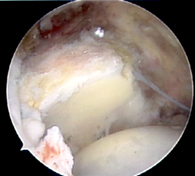

Hip labrum allograft reconstruction.

The hip labrum is a gasket-like cartilage structure that lines the acetabulum, or hip socket. Among its many important functions, the labrum helps to keep the hip stable and prevents the hip from developing arthritis. When patients present with extensive labrum tears or have large calcifications within the labrum, surgical repair of the labrum may not be possible. These patients may instead benefit from a surgical reconstruction of the labrum whereby a new labrum is created and grafted into the hip. A labrum reconstruction can be made from tissue procured from around the hip such as the iliotibial band or from allograft tissue. Using an arthroscopic technique through small key-hole incisions, the labrum can be sewn onto the acetabulum rim. The graft can be used both as an augment and placed next to the patient’s native labrum or to fill a labrum defect. Studies have shown that labrum reconstructions can successfully reduce patient-perceived pain and improve hip function. To see if you are a candidate for a hip labrum reconstruction, contact your orthopedic surgeon.